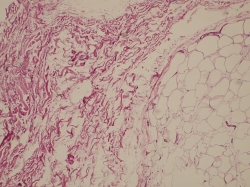

Para realizar un correcto tratamiento es necesario identificar la etiología y, solo en caso de no tener un diagnóstico de certeza, vamos a reconocer la artrofibrosis como causa de la rigidez, como un proceso de metaplasia del fibrocartílago con incremento de la fibrosis intersticial(13)(14)(Figuras 2 y 3). La historia clínica ayuda a pensar en los problemas de cicatrización, la presencia de infección superficial en el postoperatorio inmediato, los traumatismos y en la aparición de una rigidez(15)(16). Un cuadro que aparece en el postoperatorio inmediato lleva a pensar que se trata de un error quirúrgico o una rehabilitación inadecuada, mientras que en el caso de una rigidez de aparición tardía, tras un periodo de movilidad satisfactoria, nos encaminará a un proceso de infección latente o descementación.

Figura 2. Patrón intersticial normal de la grasa de Hoffa.

Figura 3. Patrón de fibrosis intersticial del paquete adiposo de Hoffa en rodilla rígida.